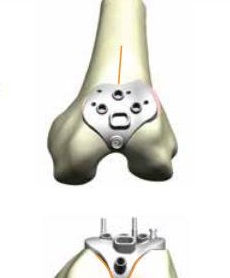

Η οπίσθια επιφάνεια της επιγονατίδας και η πρόσθια του μηρού αντικαθίστανται ανάλογα του μεγέθους και της ανατομίας του γόνατός σας με το κατάλληλο εμφύτευμα. (εικόνα 9 ) Ειδικά όσον αφορά τις οστεοτομίες στην πρόσθια επιφάνεια του μηρού, η τεχνική και οι χρησιμοποιούμενοι οδηγοί έχουν επίσης εξελιχθεί σοβαρά. (εικόνα 10 εικόνα 11 και εικόνα 12)